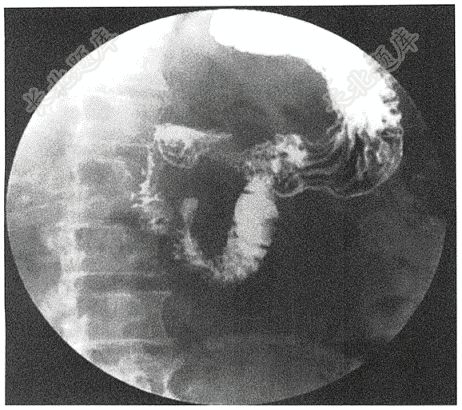

- 简答题患者女,35岁,上腹部不适半年余。